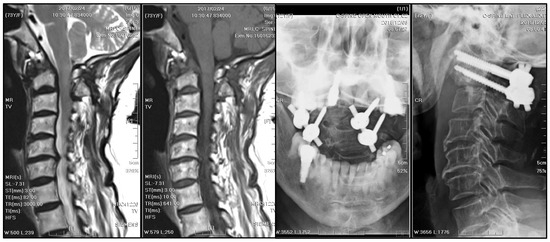

Emergent decompressive surgery was performed via a transoral approach, revealing cheese-like pus and caseous necrotic tissue, with the pathologic examination showing chronic inflammatory tissue, necrosis, and dystrophic calcification. In addition, the transoral approach facilitated prompt abscess evacuation and prevention of unnecessary damage to the nearby vital neurovascular structures. The AFB smear and culture of the specimen confirmed TB spondylitis (Figure 6). However, the sputum culture and chest radiograph did not reveal concurrent pulmonary TB. Based on local guidelines for TB treatment in Taiwan [10], a 12-month antitubercular regimen was adopted. The treatment started with ethambutol/rifampin/pyrazinamide/isoniazid for three months, then shifted to rifampicin/isoniazid for nine months. During regular follow-up visits at the neurosurgery outpatient department every three months, significant neurological improvement was observed. A substantial reduction in the size of the mass, rendering it nearly undetectable, was observed on subsequent annual MRI scans (Figure 7).

Figure 7. MRI and radiographs of cervical spine after antitubercular treatment: A 12-month antitubercular treatment regimen led to significant neurological improvement and a substantial reduction in the size of the mass, which became nearly undetectable on subsequent MRI. The stabilization remained fair.